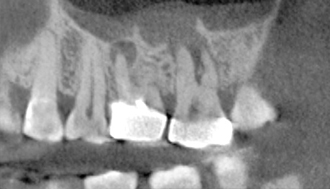

At Venkateshwar Hospital, we embrace the latest advancements in digital dentistry to improve the accuracy and efficiency of our treatments. Our digital dentistry services include digital X-rays, 3D imaging, and computer-aided design and manufacturing (CAD/CAM) technology. These innovations enable us to provide precise diagnoses, customized treatment plans, and high-quality restorations, all while minimizing discomfort and reducing treatment time.

Diagnosis, Implant planning & follow-up of implants. It can also be used for accurate measurement of dimension of lesions & planning of surgical procedures.

- Cubical Semi Tomography

- Advanced CMOS Sensor